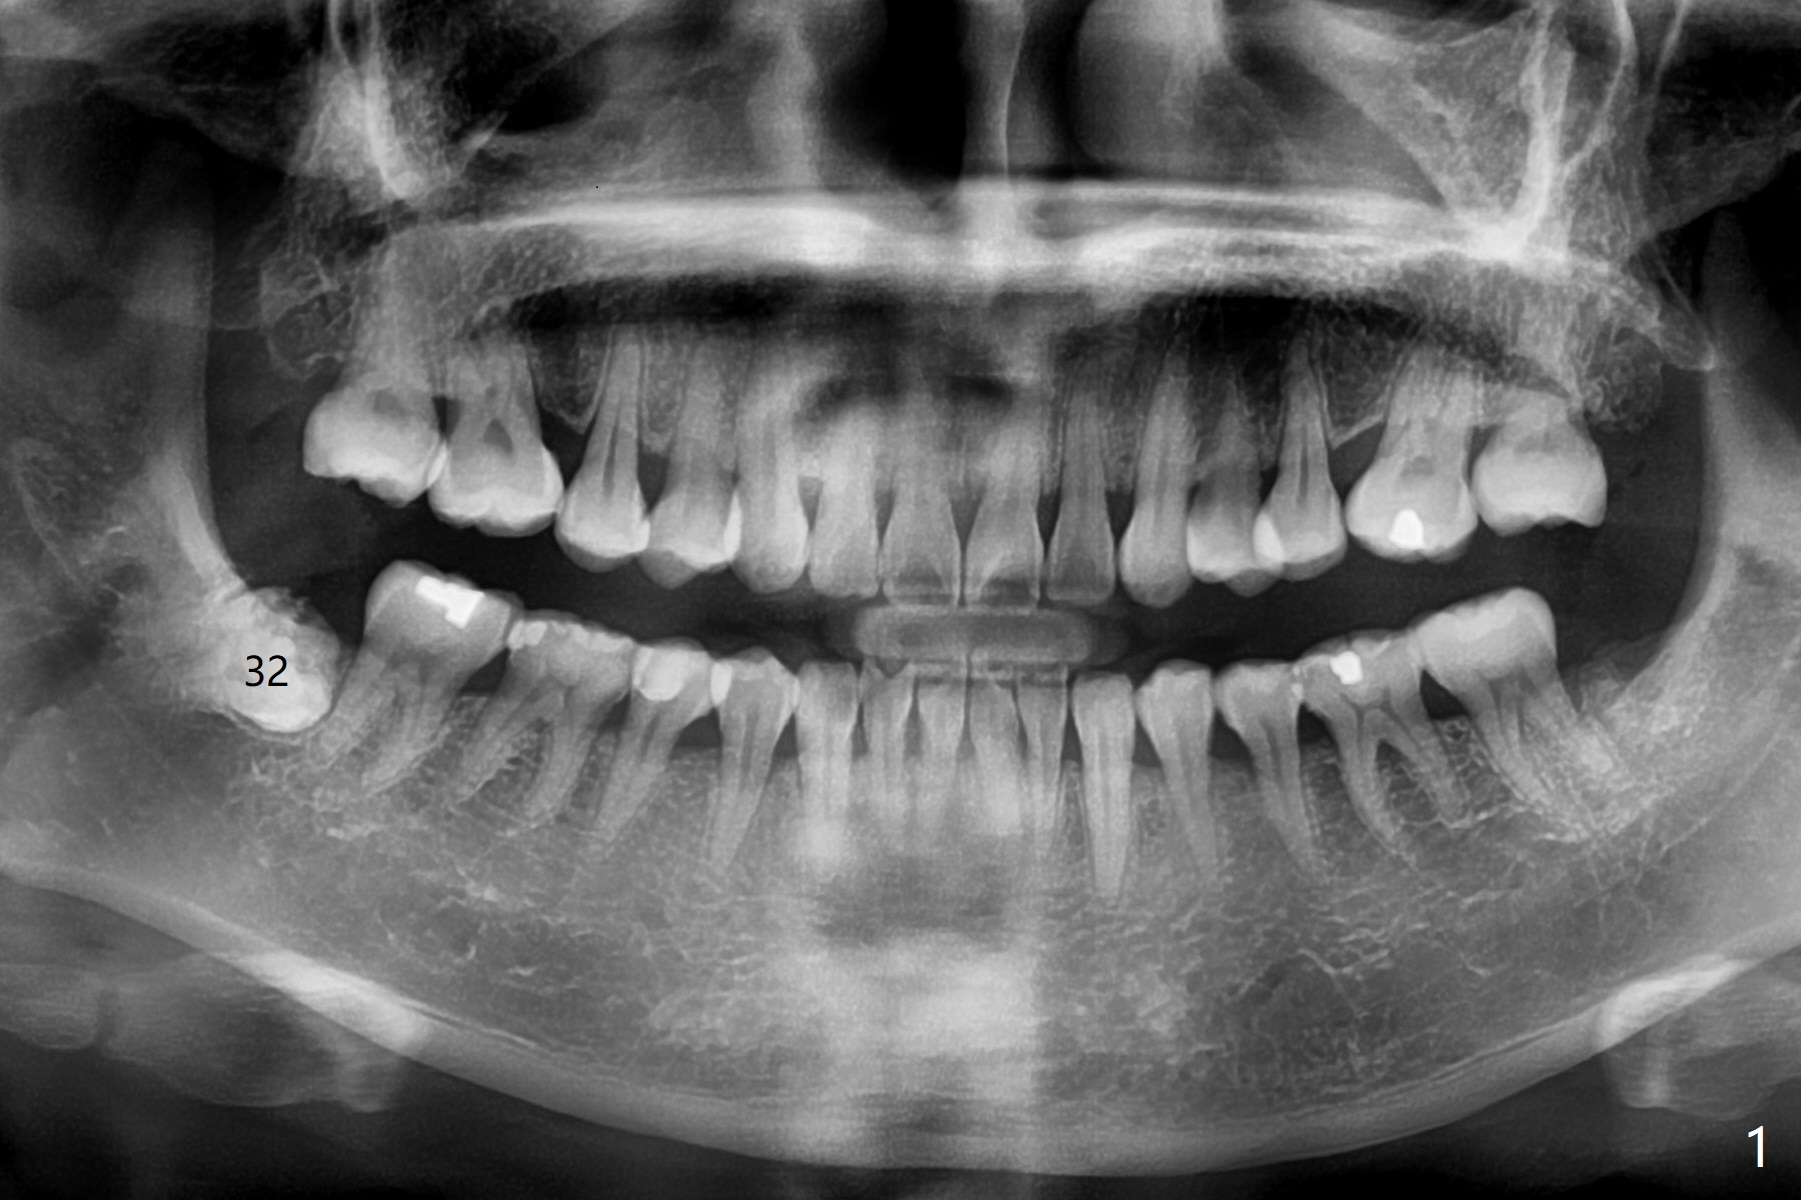

A 51-year-old woman presents to clinic because of infection in the lower right third molar (Fig.1). Although the tooth seems to be fully bony impaction, there is a sinus track with light purulent discharge after oral Amoxicillin for 5 days. In fact there is subgingival caries (Fig.2 *). The accessory incision is made mesiobuccal of #31 due to horizontal impaction. In fact the tooth is buccal and slightly mesial to #31. The impacted tooth requires several sections to be removed. Osteogen Plug is placed because of the thin bone between #31 and 32 (Fig.3 O).